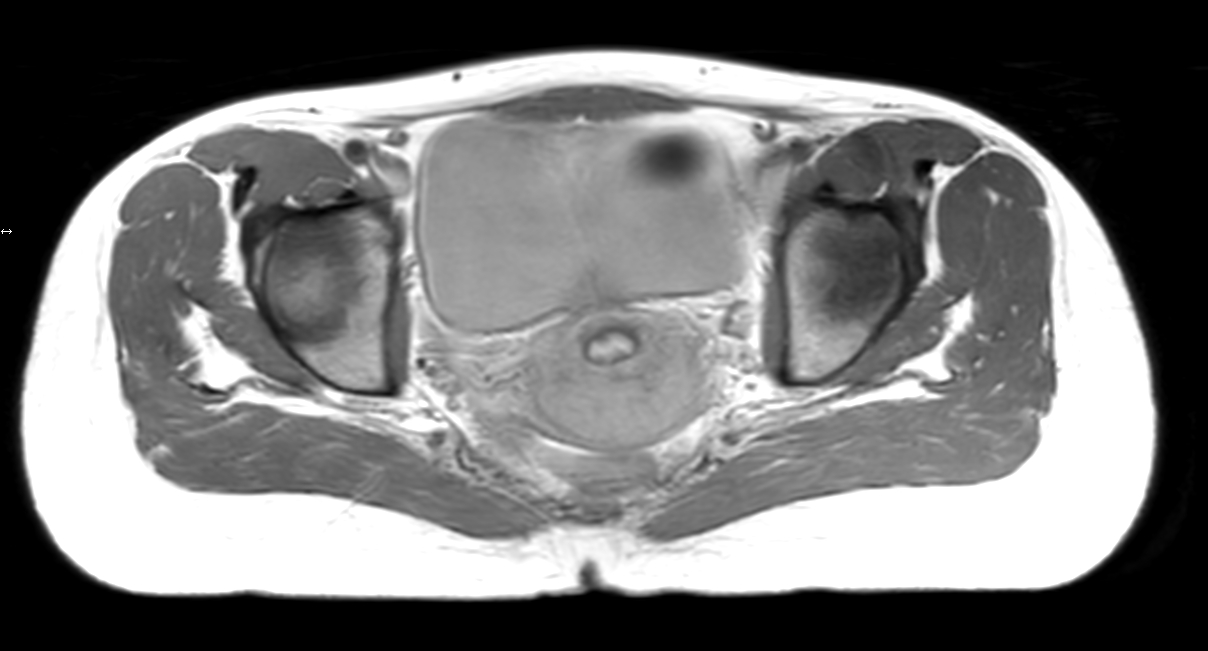

Patient diagnosed with cervical cancer referred for external beam radiotherapy. Three MRIs with different bladder filling were acquired: Half full (mid), empty and full bladder. Patient was imaged at Ingenia MR-RT 1.5T using FlexCoverage Anterior Coil in combination with the integrated Posterior Coil.

Axial T2w TSE mid